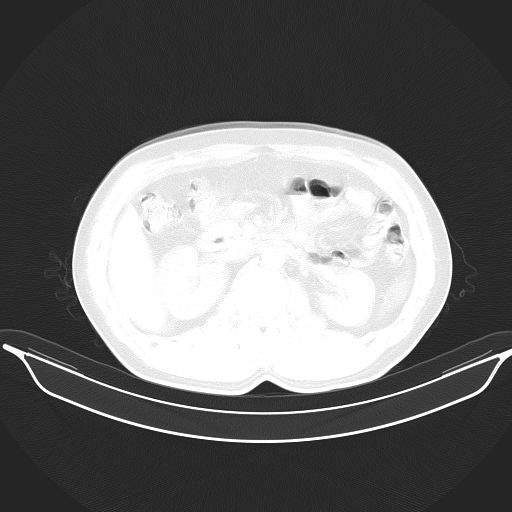

标题: CT25490:男,40岁,体检发现;无其它不适。 [打印本页]

标题: CT25490:男,40岁,体检发现;无其它不适。

考虑右下肺周围性肺癌并肺内多发转移,纵隔淋巴结转移!

支持 !考虑右下肺周围性肺癌并肺内多发转移,纵隔淋巴结转移,(气管前腔静脉后,隆突下,主动脉弓下都有了)

1、均为转移,原发灶不在肺内。2、肺癌肺转移。